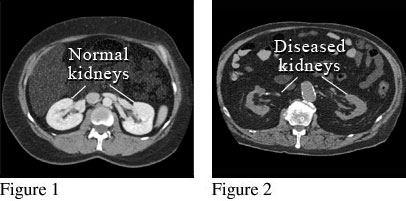

CT Scan of Damaged Kidneys